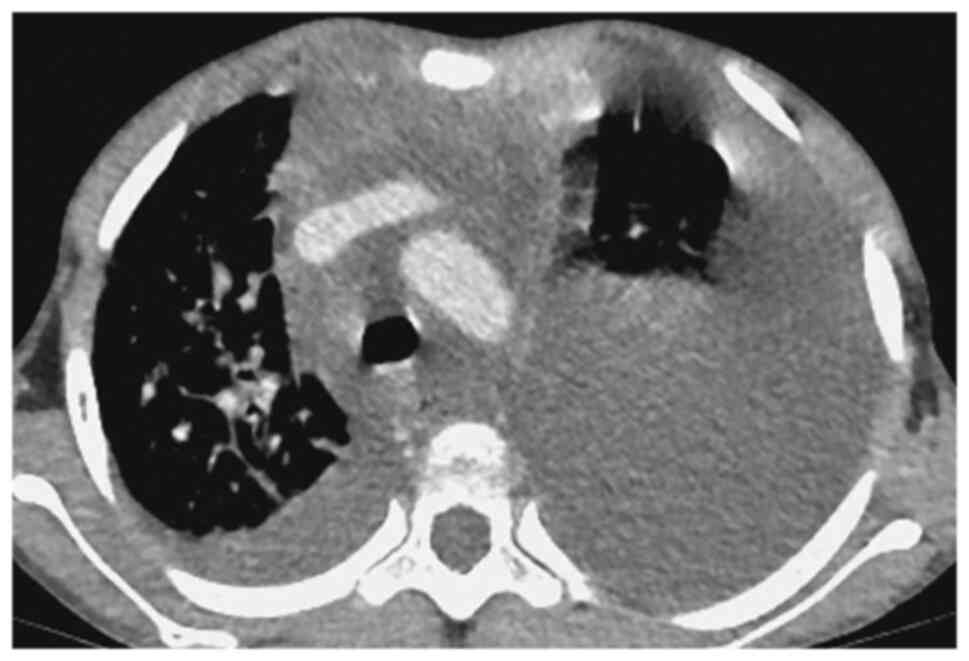

Laboratory examinations revealed severe microcytic hypochromic anemia, with hemoglobin value of 80 g/l. T-SPOT showed no abnormality. Blood and pleural effusion cultures were negative. The pleural fluid test suggested chylothorax. Contrast-enhanced chest CT (Figs. 1 and 2) showed multiple lymph nodes in bilateral cervical roots and mediastinum, which were fused into clusters, and the trachea and mediastinal great vessels were surrounded. Furthermore, there was multiple thickening of interlobular septa in the right lung, multiple inflammations in both lungs and atelectasis in the left lung, and massive pleural effusion on the left side. Positron emission tomography (PET)-CT showed soft tissue thickening around the trachea, blood vessels, and thyroid gland in the lower neck and the mediastinum, especially in the anterior and superior mediastinum. The pulmonary interlobular septum was significantly thickened, and the bronchial vascular bundle was thickened, accompanied by multiple patchy shadows of increased density and consolidation. The pleural effusion of the child was chylous (Fig. 3). Biopsy of the mediastinal mass revealed patchy, small lymphocytes with few thymus corpuscles. The tumor tissue was fissured and had a sparse reticular structure (Fig. 4). Immunohistochemistry results revealed the following: D2-40 (+), CD31 (+), Ki67 (1%+), SALL4 (-), SOX-10 (-), SMA (-), TDT (-), CD5 (-), CD117 (-), PLAP (-), AFP (-), HMB45 (-) and tissue changes consistent with the vascular origin of the tumor, inclined to lymphangioma.

Figure 2

Multiple lymph nodes in bilateral cervical roots and mediastinum, which were fused into clusters, and the trachea and mediastinal great vessels were surrounded.

Figure 3

Pleural effusion of the child was chylous.